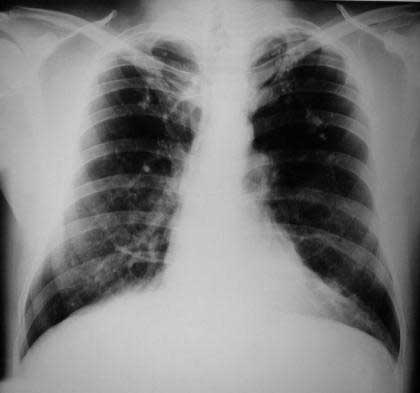

Radiología del tórax

Rx. tórax PA: Observamos el clásico tórax en tonel de un paciente enfisematoso, amplio en su base, espacios intercostales muy amplios, diafragma plano, aumento del volumen y de la trasparencia pulmonar a predominio de vértices pulmonares, en los que observamos bandas fibroticas radiopacas a predominio del lobulo superior derecho, botón aortico prominente y una silueta cardiaca elongada con reforzamiento de los hileos vasculares pulmonares.